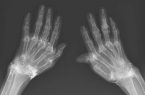

کشف صدها رشته طلای خالص در زانوی زن مبتلا به آرتروز

نادیا زکالوند: در یک مورد نادر پزشکی در کره جنوبی، پزشکان هنگام درمان درد و خشکی شدید زانوهای زنی که به آرتروز مبتلا بود، متوجه وجود صدها رشته طلای خالص در بافتهای اطراف زانوهای او و البته دستهایش شدند. درد زانوهای این بیمار علیرغم استفاده از درمانهای دارویی مانند مسکنها، داروهای ضدالتهاب غیراستروئیدی و حتی […]